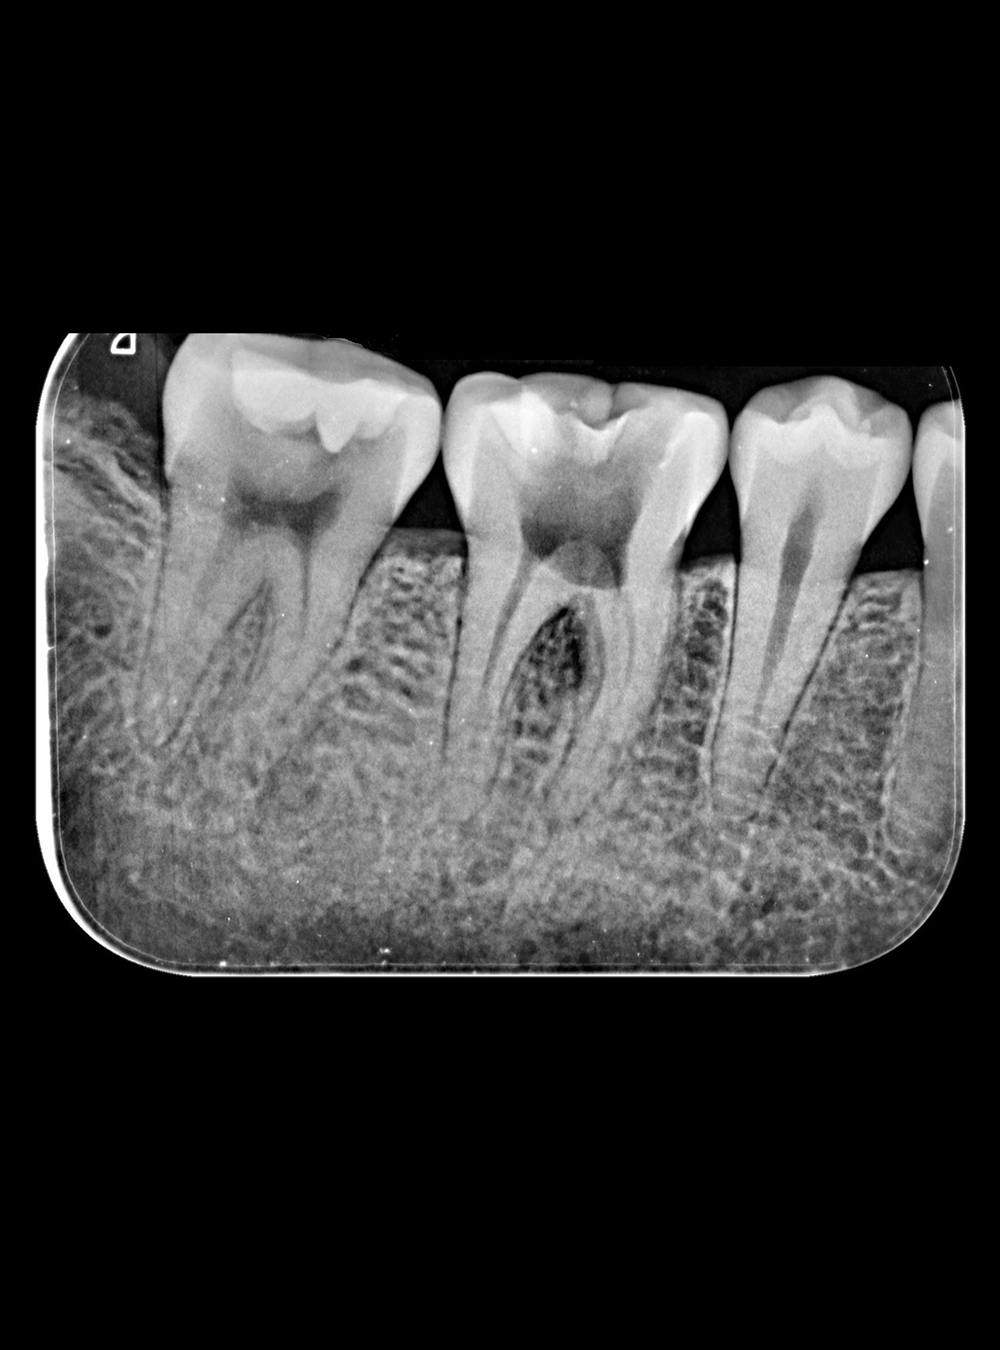

Rx Periapical Individual

Rx Serie Periapical Completa

Radiografías Intra Orales

• Periapical Individual

• Serie Periapical Completa